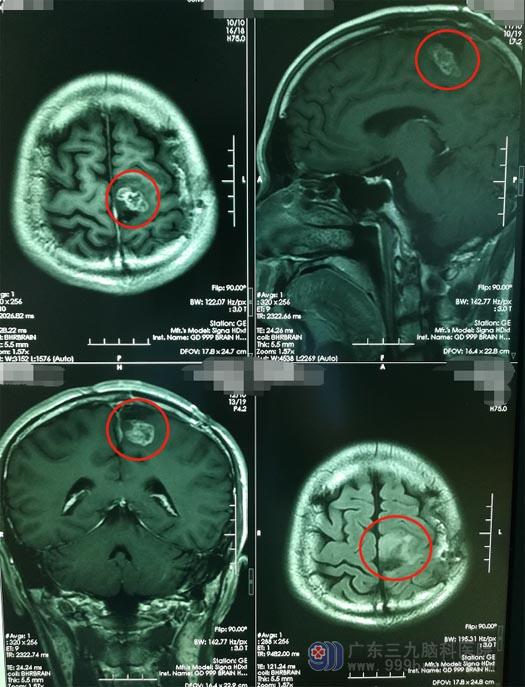

半年前,冯先生突发四肢抽搐伴意识不清,被紧急送入当地医院,予以对症处理后行头颅MR检查,提示:左侧额叶占位。于2019年12月12日行“左侧额叶占位切除术”,可手术并不是非常成功,术后出现了继发性的右侧肢体无力,伴有右侧肢体抽搐。复查头颅MR提示“肿瘤有残余”,术后病理提示“星型细胞瘤”。在医生的建议下,他又进行了放射治疗。

鲁明了解了冯先生病情后,安排他进行了更深入的检查。头颅MR检查结果显示:之前手术的位置有一个不规则花环状信号影,大小约2.4cm×2.2cm×1.3cm。神经外五科的治疗团队一致认为冯先生具有手术指征,可以进行手术将肿瘤切除。肿瘤与功能区关系密切,为了保证术后大脑的各项功能的完好,决定采用唤醒麻醉,利用神经电生理技术精确定位脑重要功能区并探询病变与功能区的关系,实施手术切除。2020年6月10日,冯先生接受了“唤醒麻醉下左额叶星型细胞瘤切除术”,手术非常顺利,术中唤醒后,冯先生可以和医生对话,可以配合医生的指令做出对应的动作。

▲手术前